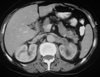

Case presentation: We present a case of a 68-year-old woman who underwent a computed tomography scan of the abdomen in the work-up for recently diagnosed hypertension. A non-enhancing left renal sinus mass was detected extending to the para-aortic space. The initial diagnosis was that of a tumor of the collecting system. Nephro-ureterectomy was performed and the pathology results revealed changes of chronic pyelonephritis.